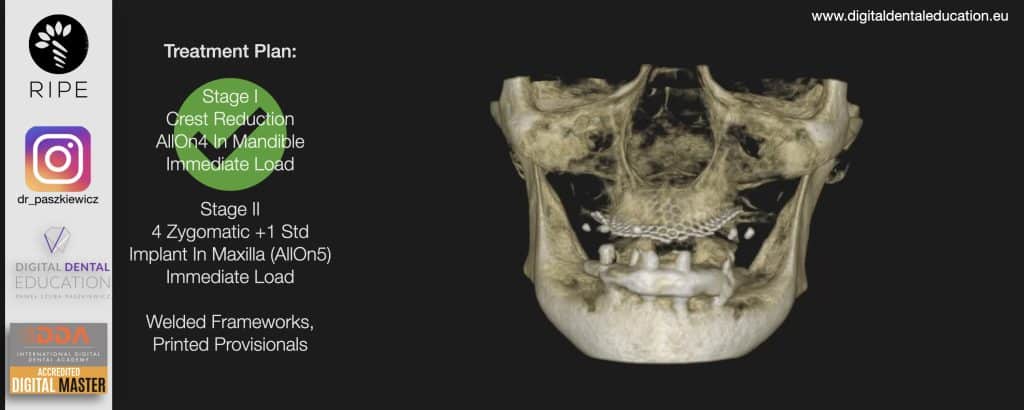

He has invented an AllonX non-impression protocol leading to final restorations post immediate implant full-arch loading, incorporated with desktop scanner (MEDIT) and ModJaw capturing of natural patient’s functional and mastication movements.